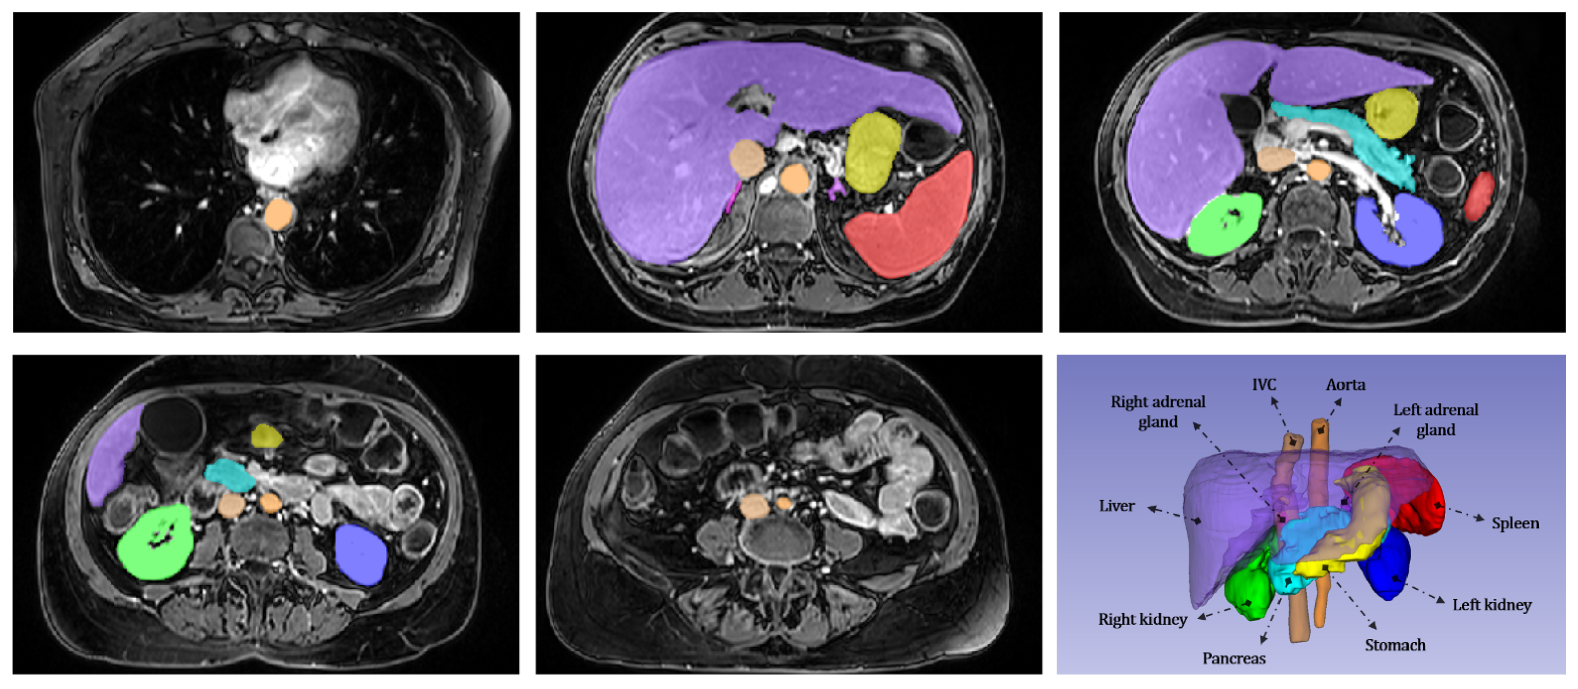

Refer to caption

Figure 1: We curated a subset of the Duke Liver dataset consisting of 40 volumes, 10 each from pre-contrast T1, arterial T1w, venous T1w, and delayed T1w series. 10 common abdominal organs (bottom right) were manually segmented in these volumes and verified by a senior board-certified radiologist. Examples of the manual segmentations for these structures at different slices (from superior to inferior) in one scan are shown.